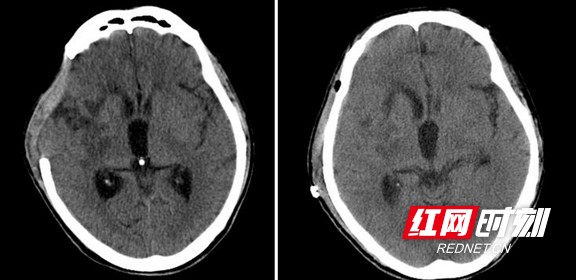

患者颅骨修补前、修补后的头部影像。

4月19日,周某再次入住湖南省人民医院神经外一科病房,准备接受颅骨修补手术。不过修补的材料不是通常使用的钛网,而是他自己的颅骨。原来,在上次手术中,医生将取下的颅骨埋植于患者腹部皮下,让它保持活性和无菌环境。此次手术就是将埋植的骨头取出,“回填”到颅骨缺损部位。

完善术前相关检查排除手术禁忌症后,黄萌异团队于4月30日在全麻下为周某施行“自体骨颅骨修补、自体骨腹壁皮下取出术”。手术过程顺利,患者于术后第7天伤口拆线,5月8日康复出院。